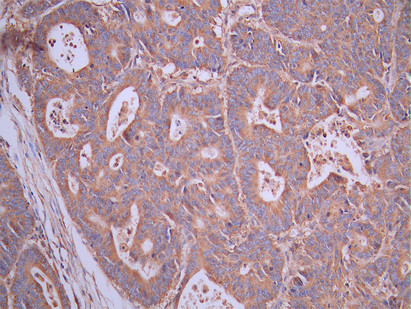

IHC image of CSB-RA057250A0HU diluted at 1:100 and staining in paraffin-embedded human colorectal cancer performed on a Leica BondTM system. After dewaxing and hydration, antigen retrieval was mediated by high pressure in a citrate buffer (pH 6.0). Section was blocked with 10% normal goat serum 30min at RT. Then primary antibody (1% BSA) was incubated at 4°C overnight. The primary is detected by a Goat anti-rabbit polymer IgG labeled by HRP and visualized using 0.05% DAB.